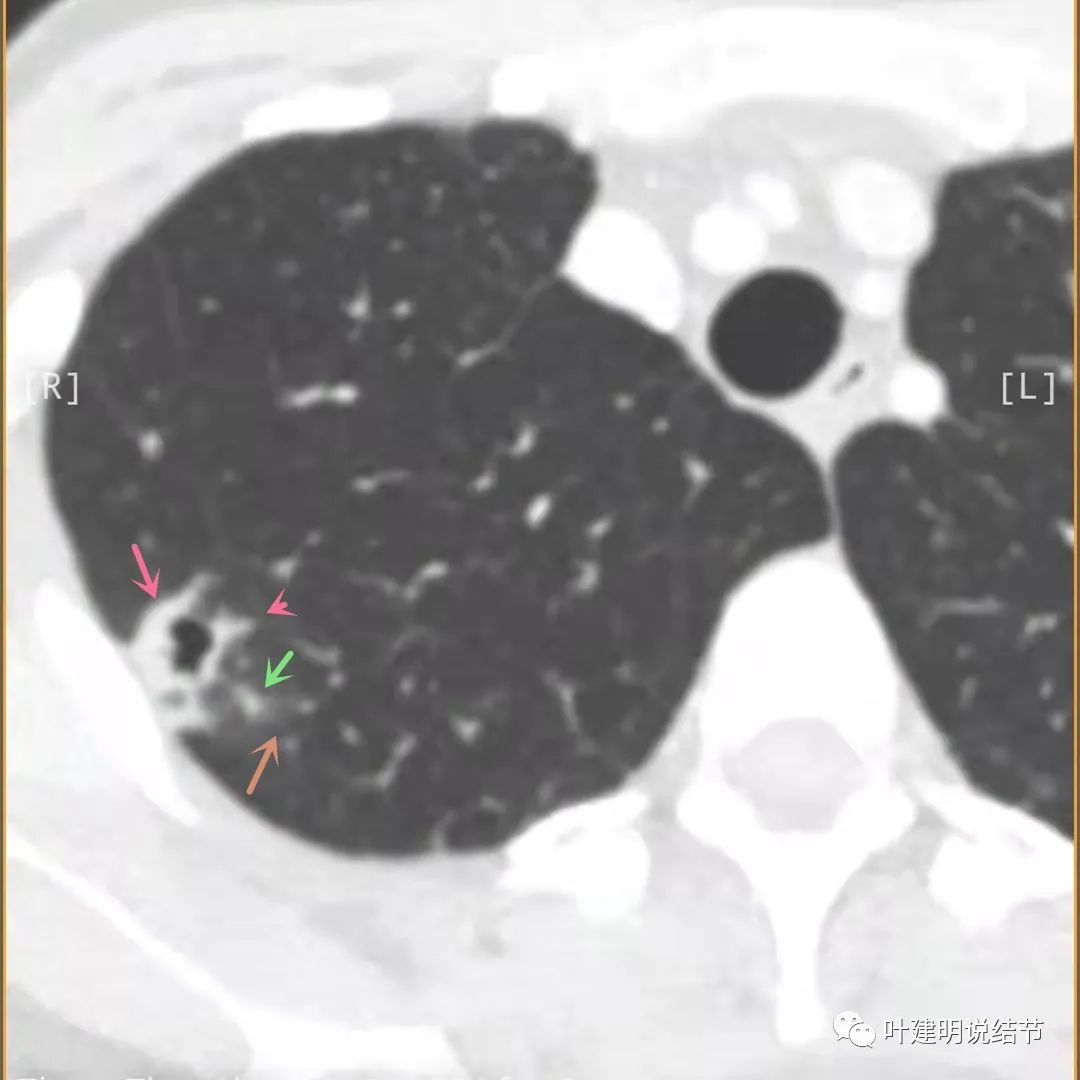

上面是她提供的病史资料,其中最重要的是PPD强阳性!其他主要看影像,我们先来看她2020年7月份的平扫片子(由于片子较多,详细展示是为了同道分析,我在影像特征描述上将只选取部分加以说明):

右肺尖偏实性结节(粉色箭头),邻近胸胸膜明显增厚不平,且广基附在胸壁上(蓝色箭头)

有卫星病灶(绿色箭头)